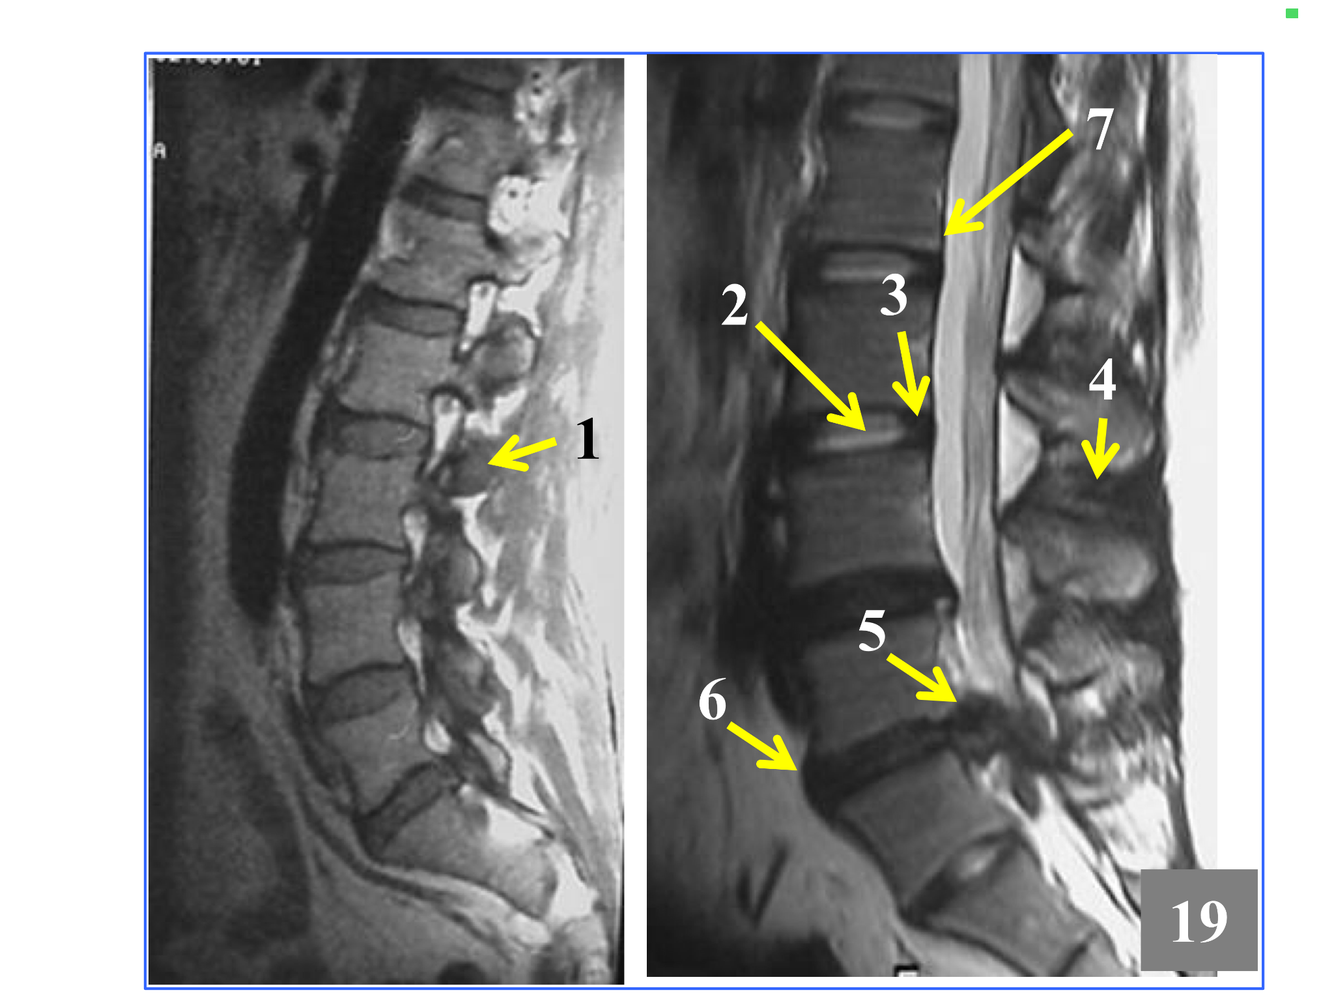

* The stack of inferior and superior articulating processes, and the zygapophyseal joints they form

*Comprised of the inferior and superior articulating processes, and the zygapophyseal joints they form

*Immediately above the conus, which is at L1-L2

* Not seen in its entirety